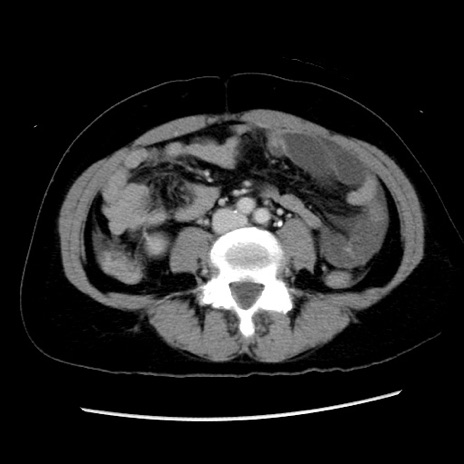

症例10(横断像)

【症例】 50歳代女性

【主訴】 腹痛

【現病歴】前日生レバーを食べた。今朝に排便あり。 昼前に突然発症の腹痛を生じ、当院救急外来を受診した。

【身体所見】 意識清明、腹部:平坦、軟、下腹部やや左を中心に圧痛・反跳痛あり、筋性防御あり

【データ】WBC 7800、CRP 0.07